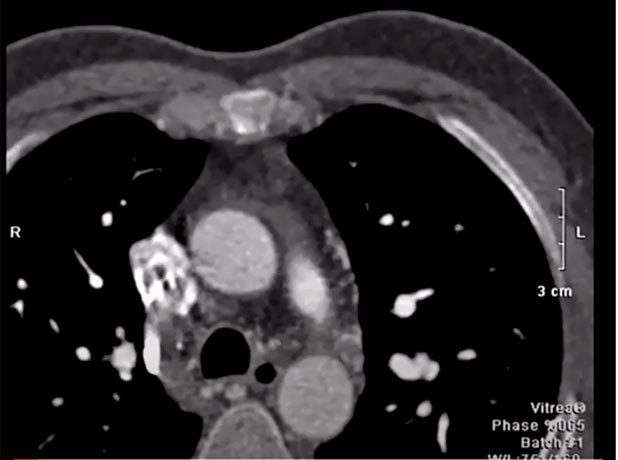

50 year patient with dyspnea sent for MSCT coronary angiography.

Look at the pulmonary arteries